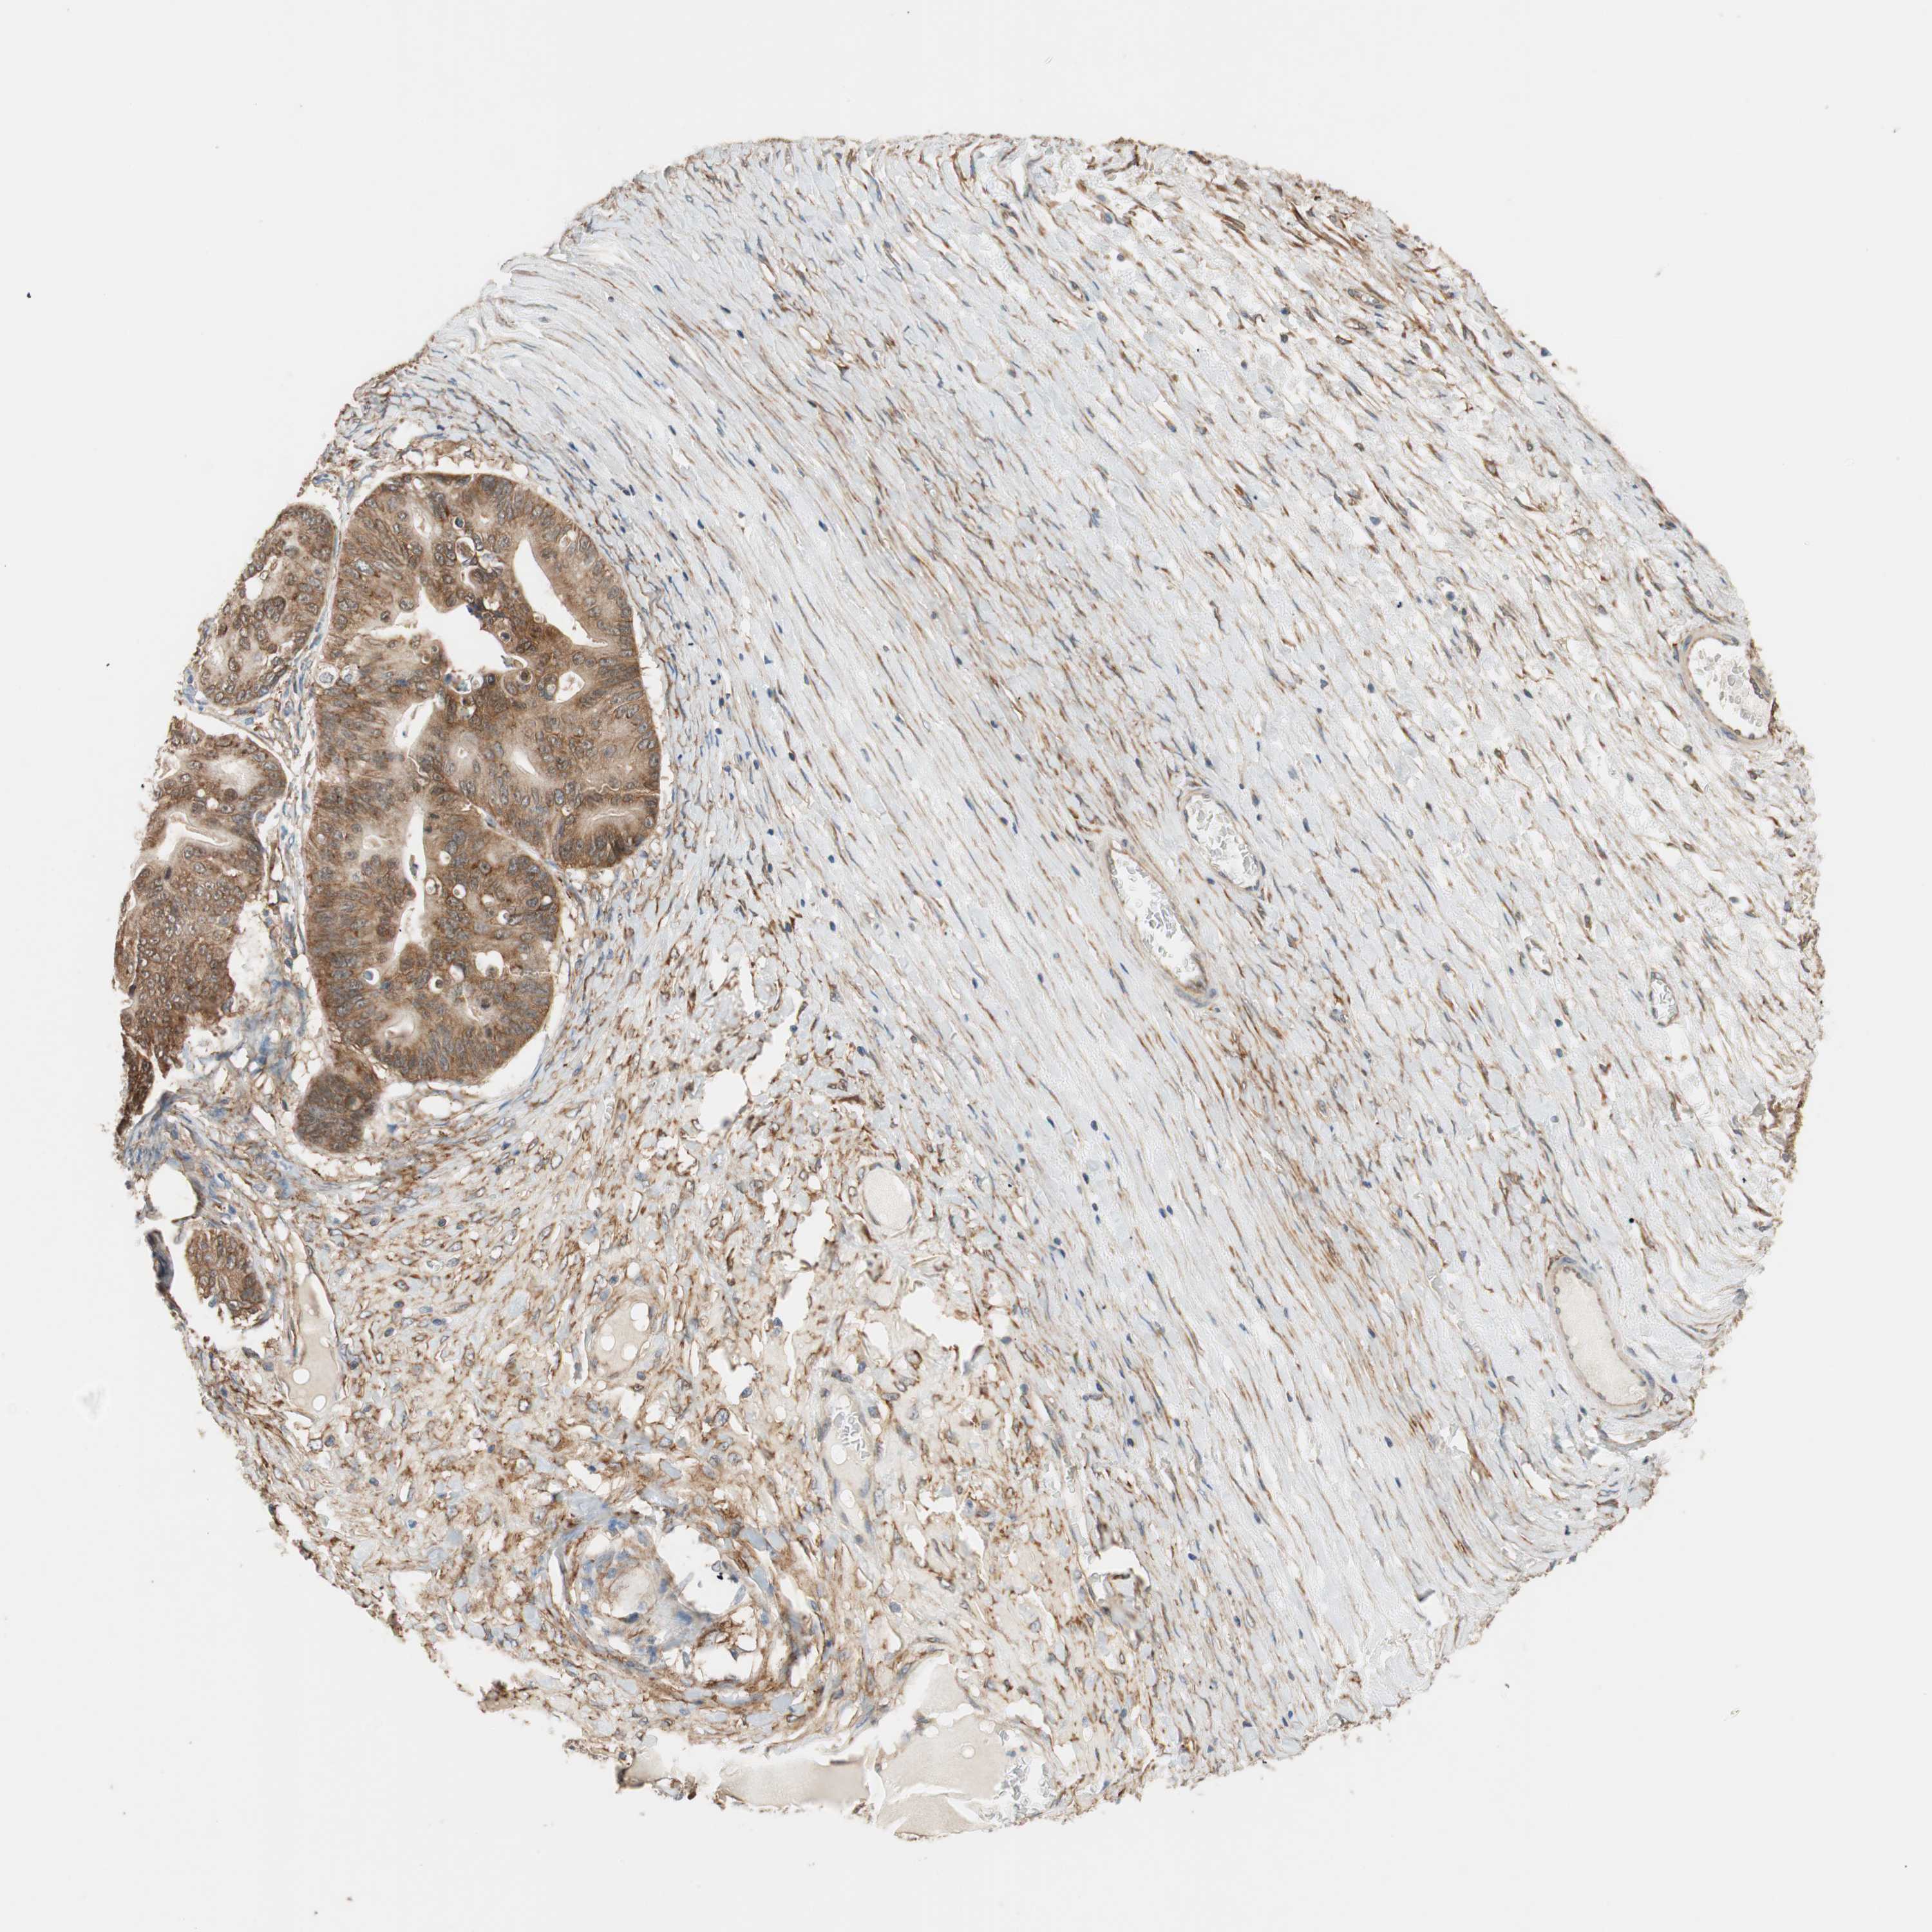

OVARIAN CANCER - Protein expressioni

A mouse-over function shows sample information and annotation data. Click on an image to view it in a full screen mode. Samples can be filtered based on level of antibody staining by selecting one or several of the following categories: high, medium, low and not detected. The assay and annotation is described here.

Note that samples used for immunohistochemistry by the Human Protein Atlas do not correspond to samples in the TCGA dataset.

Antibody stainingi

Antibody staining in the annotated cell types in the current human tissue is reported as not detected, low, medium, or high, based on conventional immunohistochemistry profiling in selected tissues. This score is based on the combination of the staining intensity and fraction of stained cells.

Each image is clickable and will lead to virtual microscopy that enables deeper exploration of all samples and also displays staining intensity scores, fraction scores and subcellular localization as well as patient and tissue information for each sample.

Antibody HPA005750

Antibody CAB005399

Carcinoma, endometroid